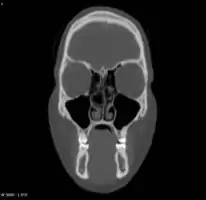

Concha bullosa

A concha bullosa is a pneumatized (air-filled) cavity within a nasal concha, also known as a turbinate.[1]

Bullosa refers to the air-filled cavity within the turbinate.[1] It is a normal anatomic variant seen in up to half the population. Occasionally, a large concha bullosa may cause it to bulge sufficiently to obstruct the opening of an adjacent sinus, possibly leading to recurrent sinusitis[1] and various head pains related to areas innervated by the trigeminal nerve.[2] In such a case the turbinate can be reduced in size by endoscopic nasal surgery (turbinectomy). The presence of a concha bullosa is often associated with deviation of the nasal septum toward the opposite side of the nasal cavity.[3]